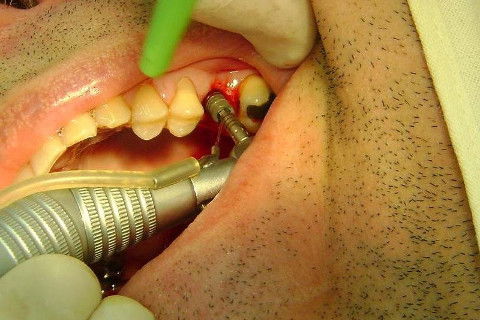

Instalação de um implante em região do 26. Utilizamos um implante cone morse Alvim Neodent 4.3 X 11,5. Foi uma cirurgia muito rápída e minimamente traumática, sem retalho e sutura.